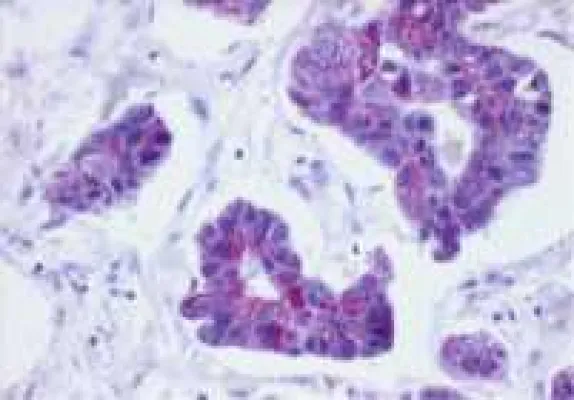

Durch die Verfolgung des Werdegangs individueller Zellen in einem sich entwickelnden Organismus können funktionale Unterschiede zwischen scheinbar einheitlichen Zellen aufgedeckt werden. Dieses Wissen ist wichtig, um die Eigenschaften hoch-regenerativer Zellen zu definieren und um diese dann für zelluläre Therapien auszuwählen. Außerdem kann so die Bildung unfähiger Zellen (welche die allgemeine Gesundheit des Organismus beeinträchtigen) vermieden werden. Die hier vorgestellte Studie stellt eine neue Methode zur Verfolgung der Geschichte von ?-Zellen vor. Genauer gesagt wurden die ?-Zellen der Bauchspeicheldrüse, im Zebrafisch analysiert. Diese ?-Zellen haben die grundlegende Aufgabe, Insulin als Antwort auf Glucose, freizusetzen. Die Autoren der Studie haben ?-Zellen mit Hinblick auf ihre Proliferation (Zellteilung), Funktion und den Zeitpunkt der Differenzierung verfolgt. Mit ihrer Studie zeigen sie, dass ?-Zellen von verschiedenen zeitlichen Abstammungen miteinander co-existieren. Dies führt zu einer Bildung dynamischer Subpopulationen, die sich im Hinblick auf ihr Potenzial zur Proliferation und funktionellen Eigenschaften, unterscheiden. In dieser Studie konnte auch zum ersten Mal gezeigt werden, zu welchem Zeitpunkt die ?-Zellen des Zebrafischs funktional sind. Durch dieses neue genetische Model werden neue Wege aufgezeigt, um zu untersuchen, wie ?-Zellen einen funktionalen Zustand erwerben.

Jüngst wurde die Heterogenität von ?-Zellen als bewiesen betrachtet und es wird angenommen, dass diese Heterogenität eine wichtige Rolle beim Fortschreiten von Diabetes spielen könnte. „Auch 20 Jahre nach Auftreten des Typ1 Diabetes, können einige ?-Zellen in der Bauchspeicheldrüse überleben. Vermutlich unterscheiden sich diese Zellen von allen anderen Zellen, was ihnen ermöglicht, sich vor dem Immunsystem zu verstecken und so einer autoimmunen Zerstörung zu entkommen“, sagt Dr. Nikolay Ninov. Die Fähigkeit zur direkten Sichtbarmachung der Evolution der Heterogenität von ?-Zellen im Zebrafisch wird zum Verständnis der dynamischen Regulation von ?-Zell-Subpopulationen auf molekularer Ebene beitragen. Dieses Wissen ist von zentraler Bedeutung für die nachfolgende Entwicklung effektiver Strategien für die Regeneration von ?-Zellen, sowie den Schutz von ?-Zellen bei Diabetes.